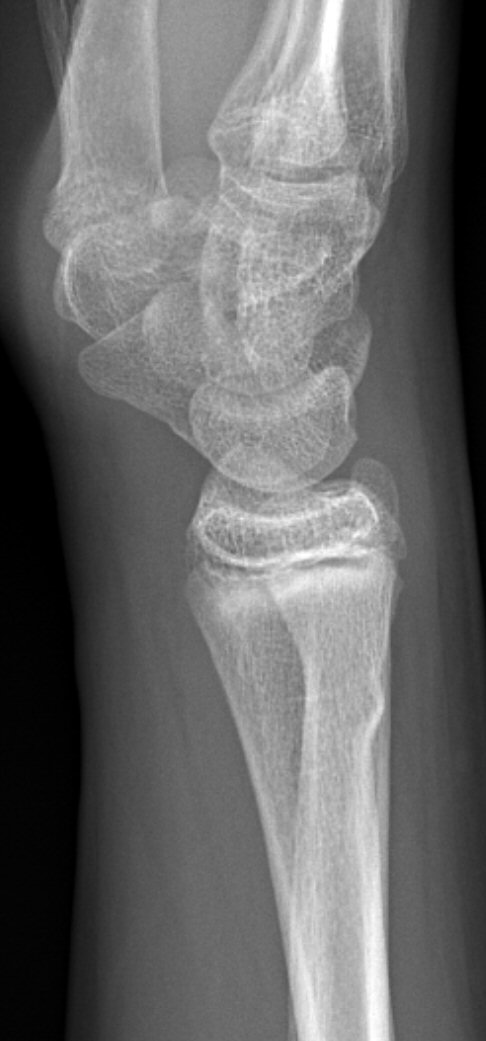

Dorsalbockad distal radiusfyseolys Salter-Harris typ 2 före och efter reposition

Dorsalbockad distal radius- och/eller ulnafyseolys (SH2)

Behandla icke-kirurgiskt om: [1]

- < 10 år för flickor, < 12 år för pojkar:

- ≤ 30° vinkelfelställning jämfört med anatomiskt läge

och

- ≤ 1/2 benbredds ad latus

- ≥ 10 år för flickor, ≥ 12 år för pojkar:

- ≤ 20° vinkelfelställning jämfört med anatomiskt läge

- ≤ 1/4 benbredds ad latus dorsalt

Icke-kirurgisk behandling:

- Semicirkulärt gips på underarmen (hög gipsskena hos små barn, det ramlar annars av), alltså bredare gips som ger trepunktstöd. Dorsalt vid dorsalbockning, volart med handleden dorsalextenderad vid volarbockning.

- Återbesök med röntgenkontroll efter 5-7 dagar [1], förutom vid odislocerad fraktur, då behövs inget återbesök.

- Vid försämrat läge men inom gränsvärde vid återbesöket: ny röntgenundersökning efter ytterligare 5 dagar. [1]

- Avgipsning i hemmet 3-4 veckor efter skadan. [1]

- Undvik risker 2 veckor efter avgipsning. [1]